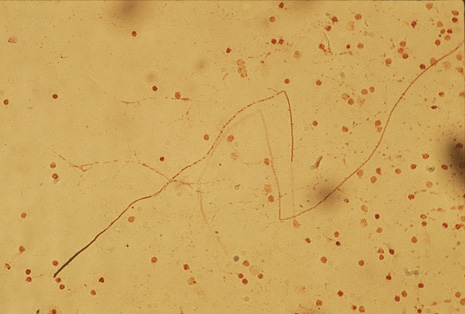

Although keratocentesis had been advocated historically as a treatment for active uveitis, it lost the attention of ophthalmologists until 1919, when Bruckner3 first examined the aqueous humor for diagnostic purposes. Laboratory techniques were revolutionized in the 20th century in areas such as: (a) evaluating very small aliquots of fluid (0.2 to 0.3 mL of aqueous or vitreous), and (b) identifying specific microbial organisms and the predominance of other cell types, antibodies, and proteins in these fluids (Figs. 1, 2, 3, 4, 5, and 6). These advancements have led to the development of diagnostic paracentesis for sight-threatening ocular inflammations that are difficult to diagnose. Witmer4 and O'Connor5 have provided strong evidence that samples of the aqueous humor reflect the antibody-producing capabilities of the iris and ciliary body, particularly when more specific antibody per unit of gamma globulin can be found on the aqueous humor than in the blood of the same patient.6–8 These determinations may be highly significant when one considers the fact that diseased tissue is being bathed in an antibody-containing fluid that is elaborated locally. For instance, in the case shown in Figure 1, the immunofluorescent antibody titer to toxoplasmosis is four times greater in the vitreous aspirate at the time of vitrectomy for repair of retinal detachment than in the plasma. These same considerations have long been recognized in syphilis of the central nervous system, wherein specific antibodies may be present in the cerebrospinal fluid but not in the blood. This is also the case with an unusual presentation of ocular coccidioidomycosis9 or toxocariasis.

Precise identification and culture of bacterial and fungal pathogens from both the aqueous humor and the vitreous fluid can be obtained. Gram's stain and Giemsa's stain smears of centrifuged specimens from the aqueous humor and the vitreous humor frequently demonstrate the bacterial or fungal causative agent. Attempts to isolate bacteria and fungi and to identify them on Gram's stain or Giemsa's stain smears have been most rewarding in the following cases: (a) postoperative endophthalmitis, (b) infection after a penetrating injury of the eye, (c) drug abuse patients with endogenous endophthalmitis (Figs. 21, 22, 23, 24, and 25), (d) patients receiving hyperalimentation, and (4) patients who are immunocompromised as a result of exogenous immunosuppressive agents.